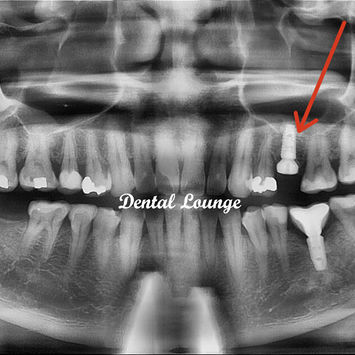

Implant Placement Surgery for Tooth #25

7. 4.5mm x 10.0mm Dentium Superline II implant placed at 30Nm.

8. Healing abutment 6.5mm (S) placed.

Post-operative CBCT taken.

Implant position and alignment very good.